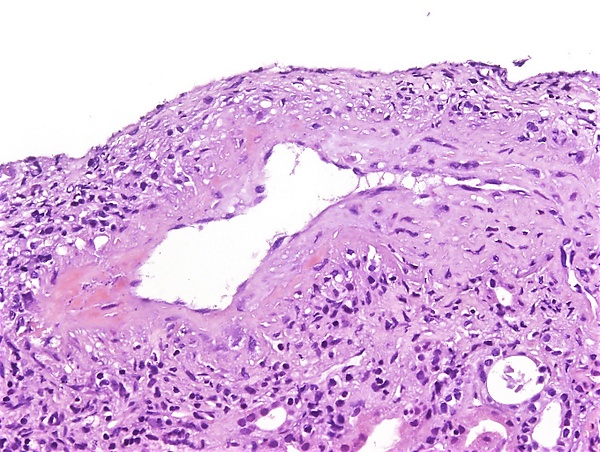

Гистологическое исследование биоптата почки: наиболее типичным является очаговый сегментарный фибриноидный некроз с разрушением базальной мембраны клубочка. Параллельно наблюдается экстракапиллярная пролиферация с образованием клеточных и фиброзно-клеточных полулуний в пространстве Боумена — Шумлянского, которые состоят из скоплений макрофагов и эпителиальных клеток. В просветах поражённых капиллярных петель часто обнаруживаются ядерный детрит и фибриновые тромбы. Активное воспаление вокруг клубочка может приводить к разрыву капсулы Боумена, иногда с формированием перигломерулярной гранулёматозной реакции. При этом для картины не характерна эндотелиальная пролиферация, типичная для иммунокомплексных ГН. В интерстиции наблюдается воспалительный инфильтрат различной интенсивности, состоящий преимущественно из лимфоцитов, гистиоцитов, плазматических клеток и иногда значительного количества эозинофилов. Васкулит поражает мелкие артерии, артериолы, капилляры и венулы, часто проявляясь как лейкоцитокластический васкулит с фибриноидным некрозом и нейтрофильной инфильтрацией. В мозговом веществе может развиваться некротизирующий васкулит сосудов прямых канальцев, что ассоциировано с интерстициальным кровоизлиянием и нейтрофильным воспаление почечных канальцев[7].

Иммунофлюоресцентный анализ биоптата почки: типичен малоиммунный тип поражения, который является характерным диагностическим признаком. При этом наблюдается слабое гранулярное свечение иммуноглобулинов (IgG, IgM, IgA) и компонентов комплемента (C3, C1q). Значительные отложения иммунных комплексов в клубочках отсутствуют, что принципиально отличает данное заболевание от иммунокомплексных ГН. В участках фибриноидного некроза и активных клеточных полулуниях выявляется выраженная флюоресценция фибрина, что отражает активность воспалительного процесса и повреждение сосудистых стенок[7].